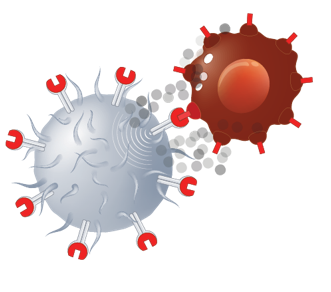

תאי Chimeric Antigen Receptor T , בקיצור: CAR-T הם תאי T, אשר עברו שינוי שמאפשר להם לזהות גידולים ולהתקיף אותם. תאי T הם תאים של מערכת החיסון (מקבוצת הלימפוציטים), אשר תפקידם הוא מלחמה בוירוסים, וכן בתאים עם שינויים סרטניים. עם זאת, אצל חולי סרטן, תאי ה T אינם מזהים את תאי הסרטן, או שאינם מסוגלים לחסלם, ומחלת הסרטן ממשיכה להתפתח בגוף.

במהלך ייצור תאי CAR-T, נאספים לימפוציטים, מהמטופל, ואלו עוברים הנדסה גנטית במעבדה. לתאי ה-T מוכנס מקטע DNA (Deoxyribonucleic Acid) אשר גורם להם לבטא קולטן המזהה את הגידול, וגם כאשר הם מתרבים, תאי הבת מבטאים את הקולטן. כאשר הם מושתלים בחזרה לחולה- הם מתקיפים את הגידול ומחסלים אותו (איור 1).

בתהליך משתמשים בתאי ה-T של החולים, ולכן זהו טיפול מותאם אישית, הדורש ייצור ספציפי של התאים לכל מטופל. עם זאת, הקולטן הוא קולטן כללי, המתאים למטרה שמשותפת בדרל כלל לכל הגידולים מאותו סוג. לדוגמה: קיימים טיפולי CAR-T כנגד לימפומה ולוקמיה של תאי B – המציגים כולם חלבון בשם CD19. תאי ה CAR-T מציגים קולטן שמזהה את ה-CD19 על הגידול, וכך הם מצליחים לזהות ולהתקיף את תאי הגידול. מאושרים בעולם טיפולי CAR-T כנגד מטרה נוספת: BCMA (B-cell Maturation Antigen), שנמצא על תאי מיילומה נפוצה, ובתהליכי פיתוח סוגים רבים נוספים של קולטנים המכוונים כנגד מטרות שונות על מגוון גידולים.